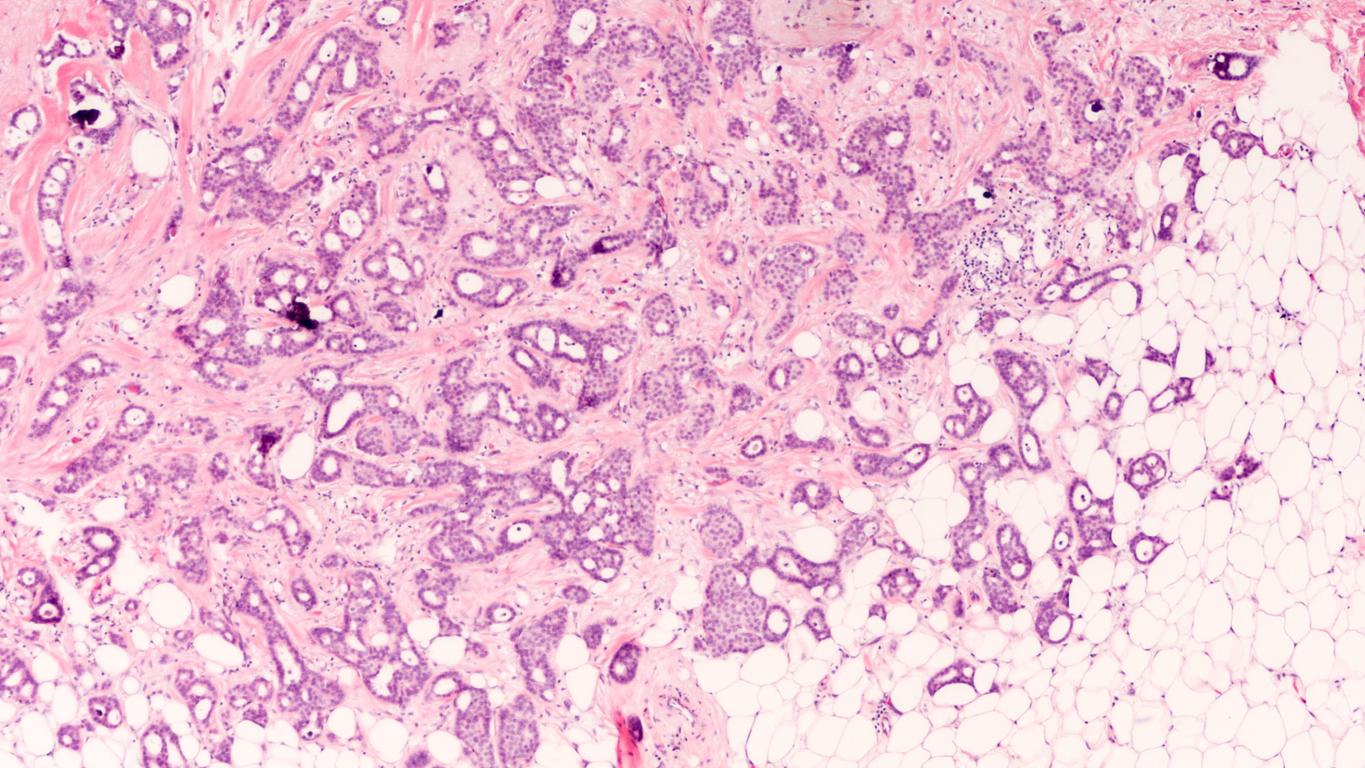

"Pour comprendre le risque de cancer du sein, vous devez d'abord comprendre les cellules mammaires normales, donc lorsque nous travaillons sur les thérapies préventives et même ciblées, nous essayons d’empêcher que les bons types de cellules se développent en cellules cancéreuses", explique Camila dos Santos, l’une des chercheuses. Pour cela, les scientifiques ont répertorié dans un catalogue toutes les cellules mammaires saines afin que, en cas de problème, les médecins puissent identifier son origine. Ils ont mené leurs travaux sur des tissus humains et de souris qui ont des profils génétiques similaires. Leurs travaux viennent d’être publiés dans la revue Journal of Mammary Gland Biology and Neoplasia.

Ce classement a été réalisé grâce à une technique connue sous le nom de séquençage d'ARN unicellulaire, qui permet d’analyser l’information génétique de chaque cellule. Ainsi, les scientifiques ont étudié l'activité de plusieurs gènes contenus dans plus de 15 000 cellules humaines et animales. "Nous avons vraiment créé tout un catalogue de nombreux gènes pour chaque population cellulaire afin de mieux les définir, développe Samantha Henry, ayant participé à l’étude. Et quand je dis qu'il y avait beaucoup de gènes, il y avait beaucoup de gènes et il a fallu y passer énormément de temps.” L’un des groupes de cellules comprenait celles réceptives aux oestrogènes - un type d’hormones féminines - qui peuvent être ciblées lors des traitements de certains cancers du sein. Mais, dans ce groupe, les chercheurs ont identifié des sous-populations de cellules, en fonction de leurs réponses aux thérapies. Référencer les différentes caractéristiques et réactions des cellules n’avait jamais été fait auparavant.